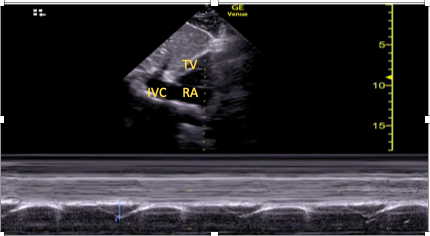

The SC window also allows a functional assessment of RV function, which is particularly important if other views are not available or are of poor quality. Visual estimation of function is possible, as is assessment of RV effects on the interventricular septum, but it should be acknowledged that the RV is foreshortened in this view, limiting assessments of size.7,8,22 Quantitative assessment of longitudinal function is also possible using the SC echocardiographic assessment of tricuspid annular kick (SEATAK).15,22,23 To perform SEATAK, the SC short axis view is obtained, M-mode is placed over the tricuspid annulus, and its excursion (kick) measured (Figure 3). This is analogous to tricuspid annular plane systolic excursion (TAPSE) in the apical four-chamber window. There will likely be an element of misalignment with the M-mode cursor and movement of the tricuspid annulus. Thus, SEATAK distances are lower than the equivalent TAPSE, and, as a result, SEATAK is not well validated. 23

Figure 3. Example of subcostal echocariographic assessment of tricuspid annual kick being performed using the subcostal short axis window.

TV=tricuspid valve, RA=right atrium, IVC=inferior vena cava